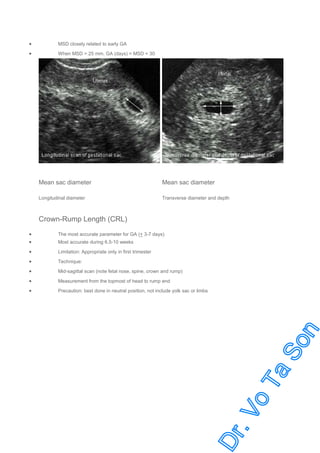

Mean Sac Diameter (MSD)

MSD : Average gestational sac diameter = width + depth + length / 3

MSD closely related to early GA

When MSD > 25 mm. GA (days) = MSD + 30

Mean sac diameter

Longitudinal diameter

Transverse diameter and depth

Crown-Rump Length (CRL)

The most accurate parameter for GA (+ 3-7 days)

Limitation: Appropriate only in first trimester

Technique:

Mid-sagittal scan (note fetal nose, spine, crown and rump)

Measurement from the topmost of head to rump end

Precaution: best done in neutral position, not include yolk sac or limbs

Most accurate during 6.5-10 weeks